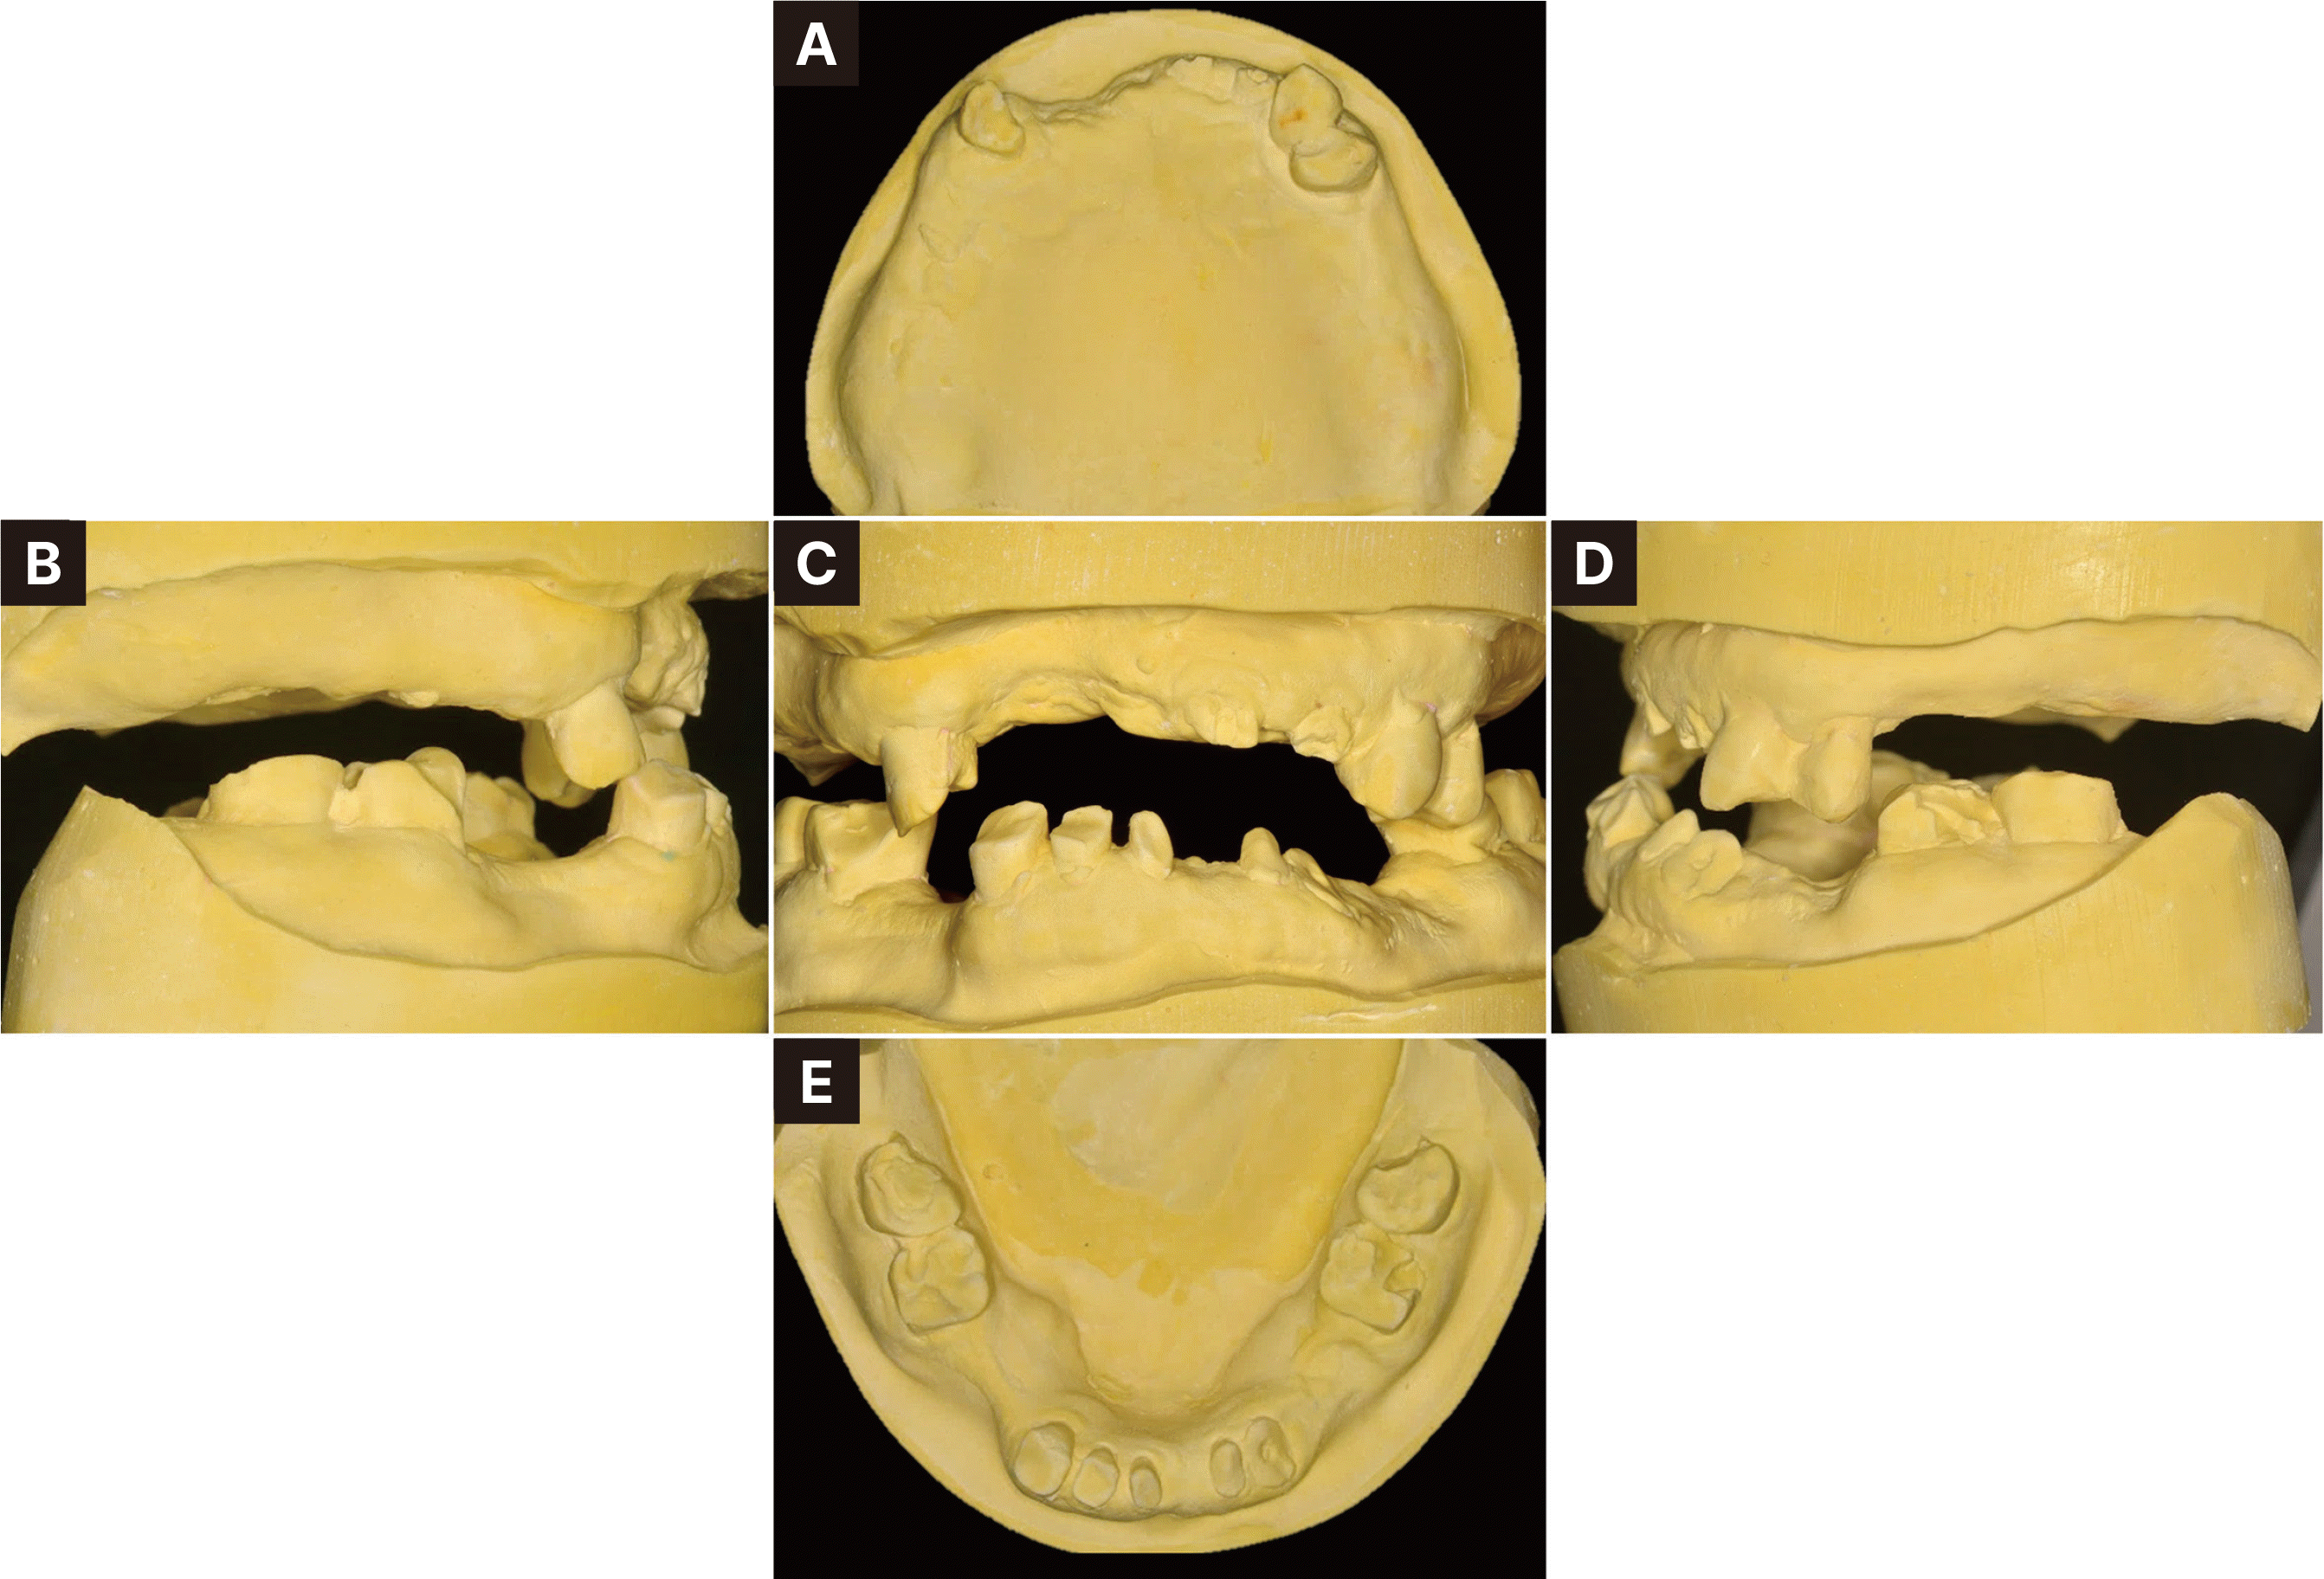

Fig. 3

Pre-operative intraoral photographs. (A) Maxillary occlusal view, (B) Right lateral view, (C) Frontal view, (D) Left lateral view, (E) Mandibular occlusal view.

82세 남자로 다수 치아의 상실을 주소로 내원하였다. 의과력으로 고혈압, 당뇨 및 협심증 병력을 가지고 있었고, 특이할 만한 치과적 병력은 없었다. 파노라마 방사선사진 검사에서 다수의 치아 상실과 전반적인 치조골 소실을 보이나, 잔존한 치아 중 상악 양측 견치와 하악 대구치의 골지지는 양호하였으며, 대구치와 전치들의 치관파절이 있었다(Fig. 1). 좌측 턱관절에서 2016년에서 2020년까지 골변화가 의심되는 소견을 보였다. 그러나 턱관절의 통증과 불편감을 보이지 않았고 임상적으로 안정적인 턱관절 움직임을 나타내어, 적응된 턱관절 관계로 판단하여 보철치료 진행을 결정하였다. 구외 안모평가 시 발달된 저작근과 하악이 전돌된 안모를 가지고 있었다(Fig. 2). 구내 검사 시 습관성 폐구위에서 교합되는 치아가 없었으며 이에 따라, 잔존 치아들이 치조제 점막에 대합되어 뚜렷한 압흔이 관찰되었다(Fig. 3).

비가역성 하이드로콜로이드(Aroma Fine Plus, GC Co., Tokyo, Japan)를 이용하여 예비인상을 채득하여 진단모형을 제작하고, 중심위에서 알루왁스로 악간관계기록 채득 및 안궁이전을 시행하여 반조절성 교합기에 중심위 악간관계기록을 이용하여 부착하였다. 진단모형 분석 시 잔존 치근들은 지대치로 사용하기에 치질이 불충분하였으며, 그 외의 치아들도 전부관이 필요할 정도의 파절과 마모양상을 가지고 있었다(Fig. 4). 또한 구치부 지지를 상실한 전후방으로 엇갈린 교합상태를 보이며, 교합지지영역이 없는 Eichner’s index category C-1으로 분류되었다.8 Willis법을 이용한 안모분석비율과 교합안정거리(interocclusal rest distance) 측정 시 하안모가 짧았고 교합안정거리는 6 mm로 수직고경의 감소가 있다고 판단하였다(Fig. 5).